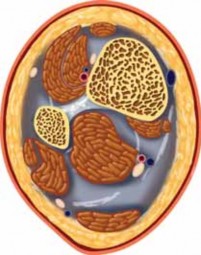

---

Anterior tibial artery and vein Extensor hallucis longus Extensor digitorum communis Anterolateral approach Deep peroneal n. Tibialis anterior tendon Anteromedial approach Tibia Fibula Peroneus longus m. Peroneus brevis m. Posterolateral approach Sural n. Sural v. Saphenous v. Posteromedial approach Posterior tibial artery and vein Tibial n. Flexor hallucis longus m. Achilles tendon ### FIG 6 • Approaches to the tibial plafond are probably best tailored to match the injury pattern. More than 90% of plafond fractures are well approached anteriorly (anteromedially or anterolaterally), but other approaches are sometimes useful.

39.

Although historically a single “utilitarian” approach was popular in the reconstruction of the tibial plafond, a variety of surgical approaches are currently used to treat these fractures ( FIG 6).